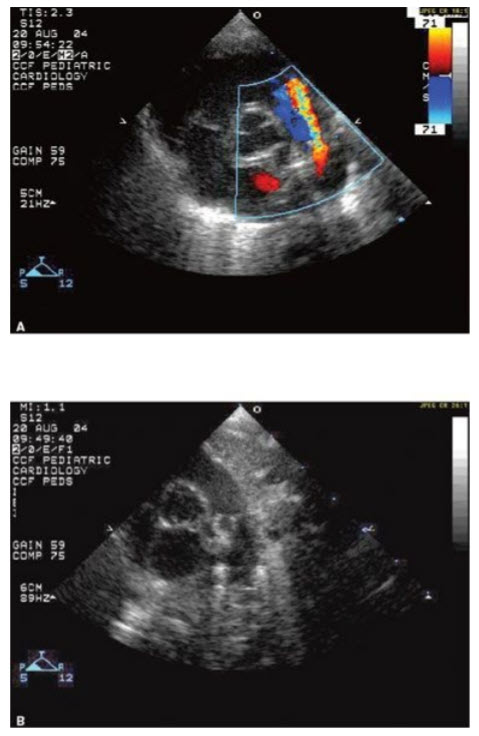

The images in Figure below A and B

are associated with which of the following?

Moderate risk of endocarditis. The images in Figure in question demonstrate a Patent Ductus Arteriosus (PDA). This is seen as the color flow into the pulmonary artery (PA). In this example, the PDA is large and its orifice can be seen in the two-dimensional (2D) images opening into the PA. The complications that can be associated with a PDA include the development of CHF and a moderate risk of endocarditis (although antibiotic prophylaxis is not recommended unless the unrepaired PDA is complicated by pulmonary hypertension/Eisenmenger syndrome causing cyanosis). The clinical manifestations of the PDA depend on the size of the left-to-right shunt. The larger the shunt, the worse the clinical manifestations. The murmur associated with a PDA is a continuous murmur (since the left-sided pressures are higher than the right side throughout the cardiac cycle), not a systolic murmur.